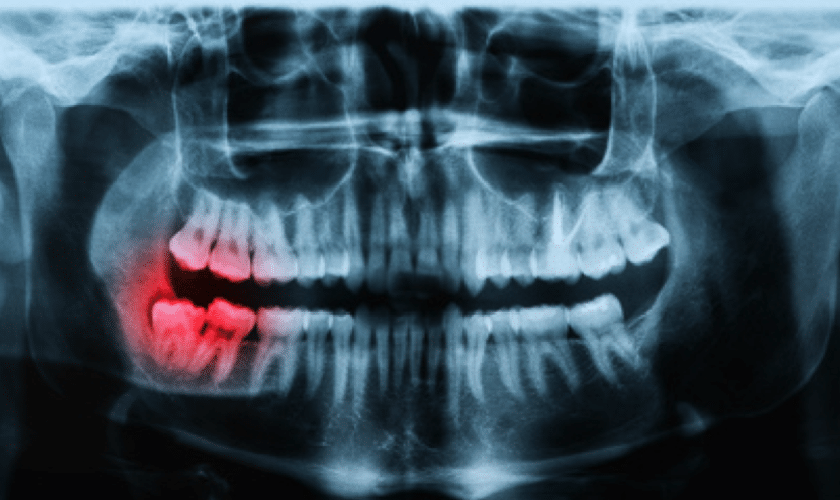

Thorough dental check-ups including digital X-rays, gum assessment, and full oral cancer screening for complete peace of mind.

Learn More

Modern digital dental X-rays for accurate, low-radiation diagnosis — essential for safe and comprehensive treatment planning.